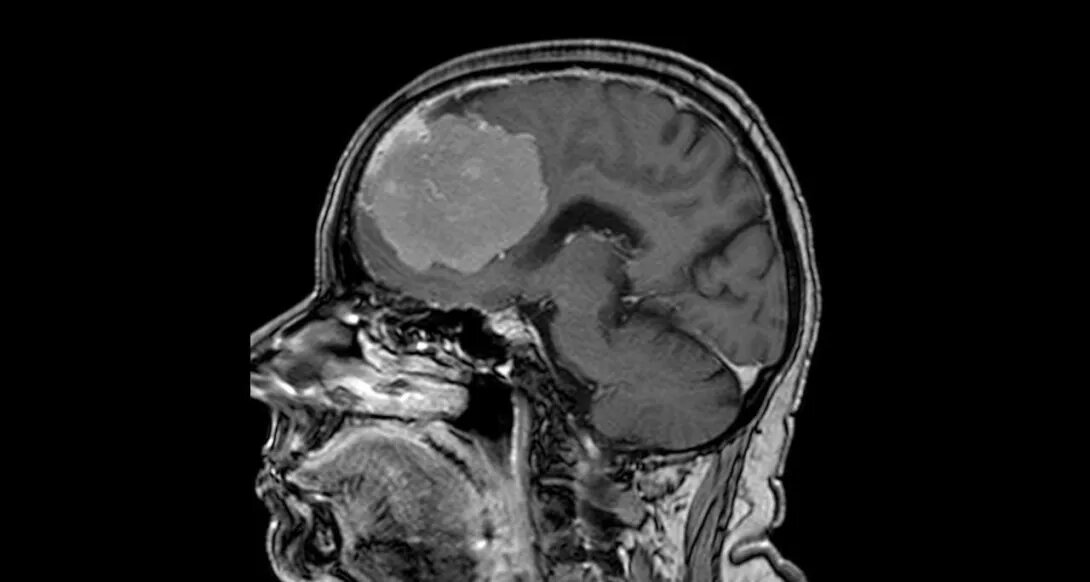

Опухоль размером с грейпфрут удалили медики воронежской БСМП №1 из мозга 80-летней пенсионерки. Операция длилась шесть часов. В настоящее время пожилая женщина находится дома, чувствует она себя хорошо. Горожанка попала в больницу с подозрением на инсульт. Женщина жаловалась на слабость в правой руке, проблемы с речью. По итогу проведения обследования стало ясно, что инсульта у нее нет. Однако есть внушительных размеров – 6*7*8 см – новообразованием, затронувшее обе лобных доли. Операция прошла без осложнений, риск которых был велик, учитывая размеры опухоли. В процессе могли быть задеты жизненноважные сосуды, участки, отвечающие за речь и движение. Неврологическая симптоматика у пациентки пропала сразу после проведения хирургического вмешательства, отмечают в пресс-службе регионального департамента здравоохранения. Фото – региональный Минздрав. Не пропустить важное в ДЗЕН 36ON

Горожанка попала в больницу с подозрением на инсульт. Женщина жаловалась на слабость в правой руке, проблемы с речью. По итогу проведения обследования стало ясно, что инсульта у нее нет. Однако есть внушительных размеров – 6*7*8 см – новообразованием, затронувшее обе лобных доли.

Операция прошла без осложнений, риск которых был велик, учитывая размеры опухоли. В процессе могли быть задеты жизненноважные сосуды, участки, отвечающие за речь и движение.

Неврологическая симптоматика у пациентки пропала сразу после проведения хирургического вмешательства, отмечают в пресс-службе регионального департамента здравоохранения.